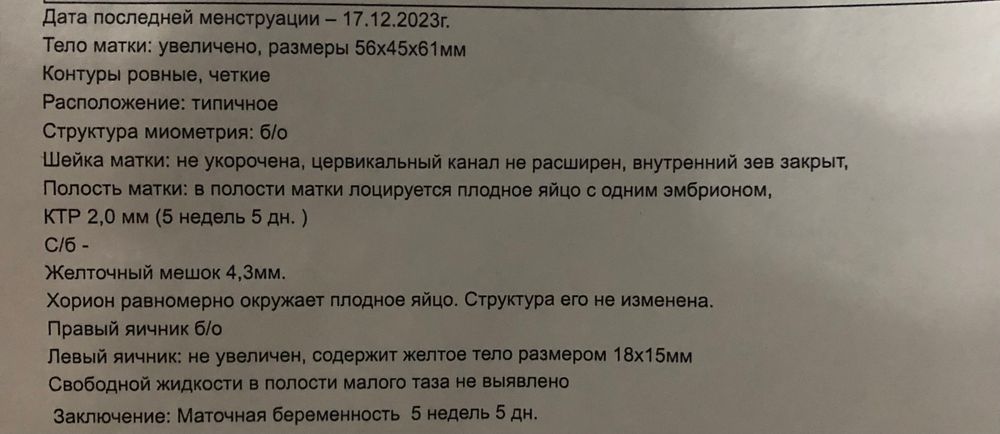

Киньте плз фото вашего УЗИ 5-5,5 недель

УЗИ, КТГ, доплерХочу посмотреть как оно должно "нормально" выглядеть 🙏🏻

Алена, 2 дня назад мне по УЗИ доктор предположил 5 с чем-то недель, фото УЗИ не дал, но мне визуально показалось что желточный мешок большой какой-то. Хочу понять, может так и должно выглядеть